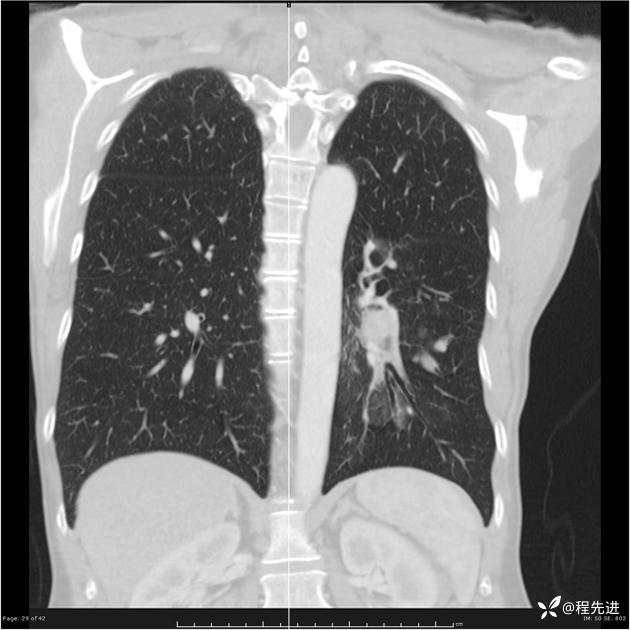

病例女,53岁,气管、左主支气管、下叶支气管内结节,乳头状瘤?期待你的精彩解读

女,53岁

乳头状瘤?